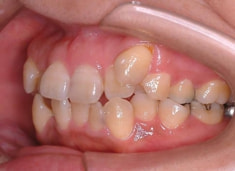

治療前

治療後(2年5ヶ月後)